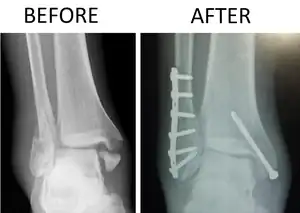

| X-ray of trimalleolar fracture repair before and after ORIF surgery | |

Surgical repair using open reduction and internal fixation is generally required, and because there is no lateral restraint of the foot, the ankle cannot bear any weight while the bone knits. This typically takes six weeks in an otherwise healthy person, but can take as much as twelve weeks. Non-surgical treatment may sometimes be considered in cases where the patient has significant health problems or where the risk of surgery may be too great.[2]